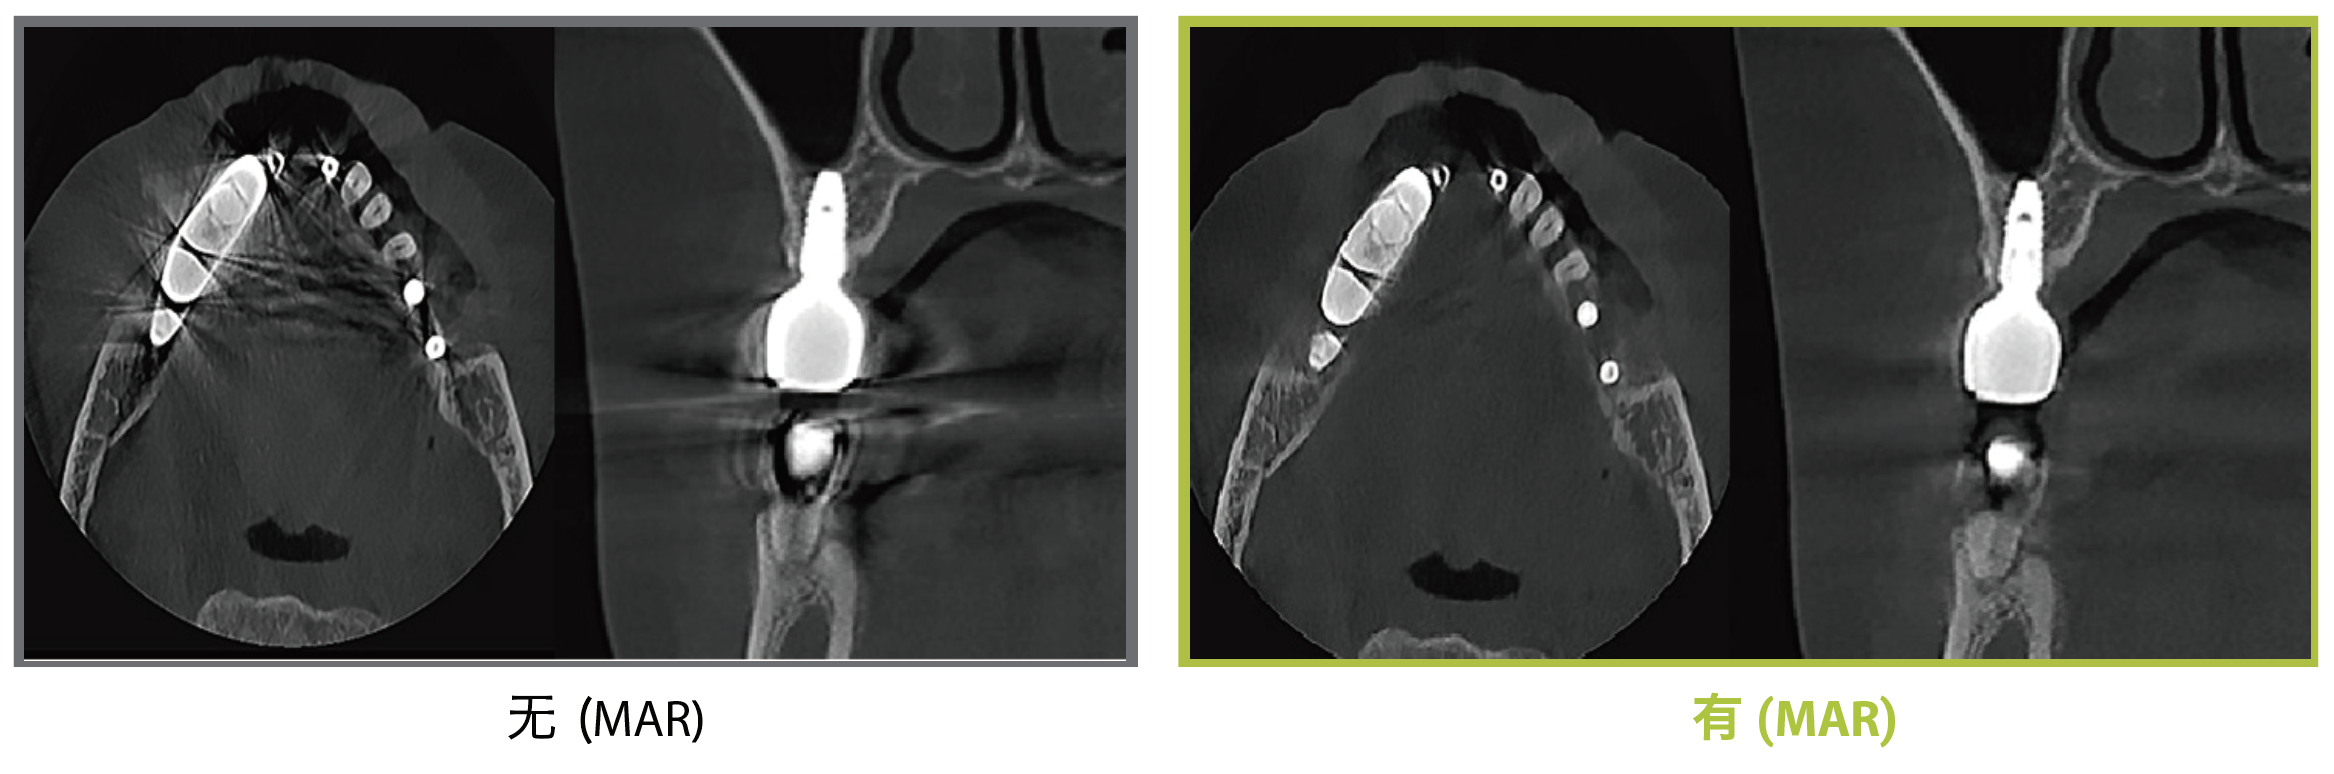

bright MAR金屬減影算法

通過實時比較的Dentium MAR技術,自動減少由植入物、填充物或修復體引起的金屬偽影。這有助于確認并降低誤診的風險。